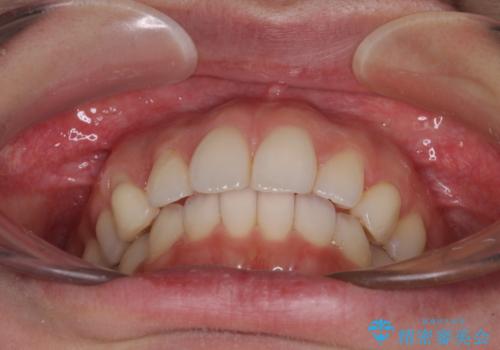

- 前歯のクロスバイトや残存している乳歯を気にして来院された患者様です。

上顎骨の幅が下顎骨よりも小さいので、拡大装置により骨幅を広げて上下関係を改善し、その後インビザラインにて歯並びを整えることとしました。

上下の骨幅を改善したことで、スムーズに歯列矯正を行うことができました。